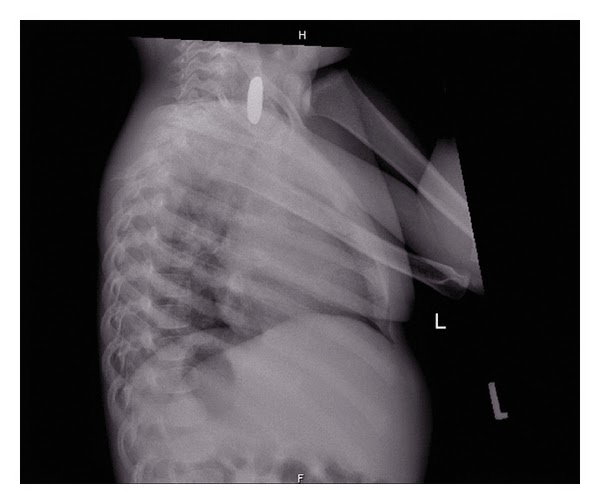

Button Battery Ingestion X Ray . A halo sign or double ring sign can be seen which eludes towards the foreign. Suspect a button battery ingestion in every presumed coin or other foreign body ingestion. A foreign body is seen at the level of the cricopharyngeus. In case of multiple coin ingestion or unclear history from parent/patient, anteroposterior (ap) and lateral radiographs may both help in differentiating coins from button batteries. A metallic foreign body projects over the right upper abdomen. If there is a known bb ingestion, x‐ray should be obtained in all patients except. The evaluation and management of button and cylindrical battery ingestion will be presented here.

In case of multiple coin ingestion or unclear history from parent/patient, anteroposterior (ap) and lateral radiographs may both help in differentiating coins from button batteries. If there is a known bb ingestion, x‐ray should be obtained in all patients except. A halo sign or double ring sign can be seen which eludes towards the foreign. A foreign body is seen at the level of the cricopharyngeus. The evaluation and management of button and cylindrical battery ingestion will be presented here. Suspect a button battery ingestion in every presumed coin or other foreign body ingestion. A metallic foreign body projects over the right upper abdomen.

20 mm lithium button battery causing an oesophageal perforation in a